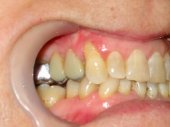

Alteraciones de los tejidos parodontales (encía, ligamento y hueso) por problemas funcionales |

Sangrado gingival espontáneo, infecciones

en las encías o movilidad dentaria debidos al desequilibrio oclusal